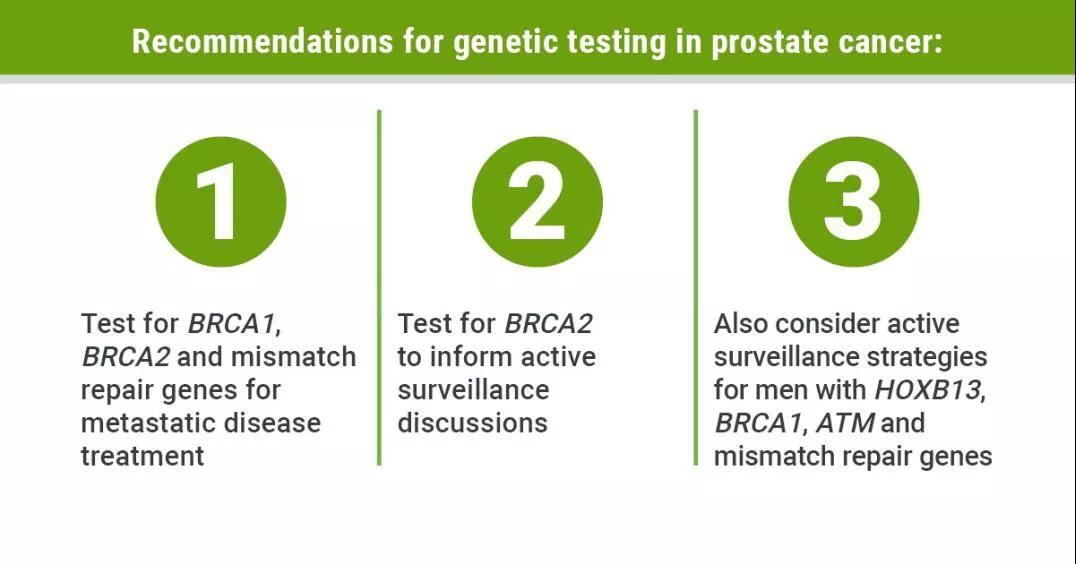

1. 新框架使前列腺癌基因检测指南“更进一步”[1] 根据2019年费城前列腺癌多学科共识会议上提出的建议,所有转移性前列腺癌患...